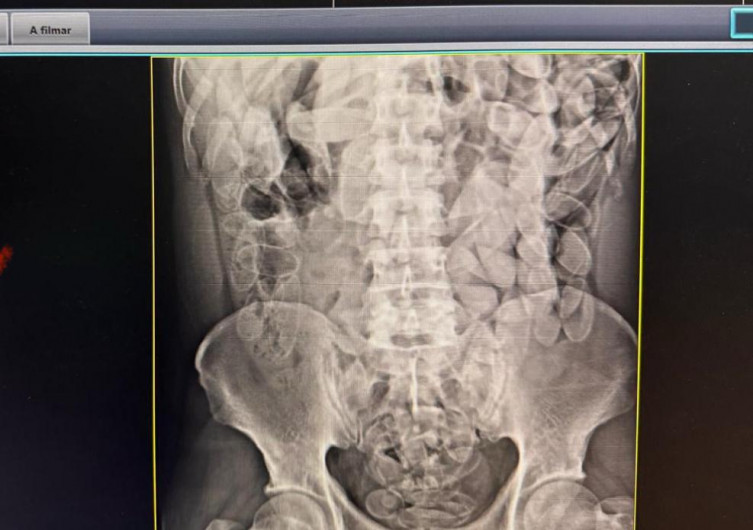

Exames mostraram que cada pessoa ingeriu cerca de 100 cápsulas de drogaOs dois homens e uma mulher foram levados para a Santa Casa e exames de raio-x confirmaram que eles haviam engolido aproximadamente 100 cápsulas de pasta base de cocaína cada um, totalizando cerca de 3,5 kg de entorpecente.